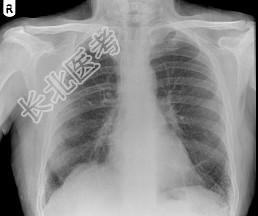

- 单项选择题62岁,男, 铸铁工,咳嗽、呼吸急促1个月, 请结合胸片,选出最可能的诊断 ( )

A、粟粒性肺结核

B、肺结节病

C、尘肺

D、肺炎

E、肺淤血